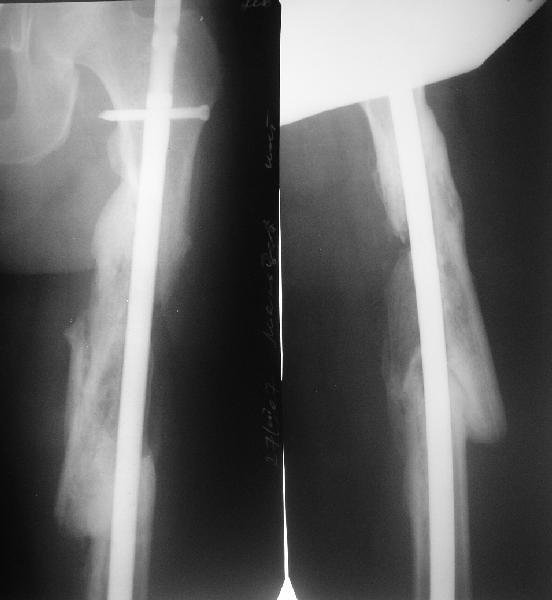

Мы бы не стали открывать, такие переломы срастаются, хотя бы и с краевым дефектом. То есть если удалять стержень потом, то сильно попозже обычного. В приложении пример. Сразу после операции и через 11 мес. Понятное дело, пациент к тому времени давно и не хромал, и функция колена была полная.